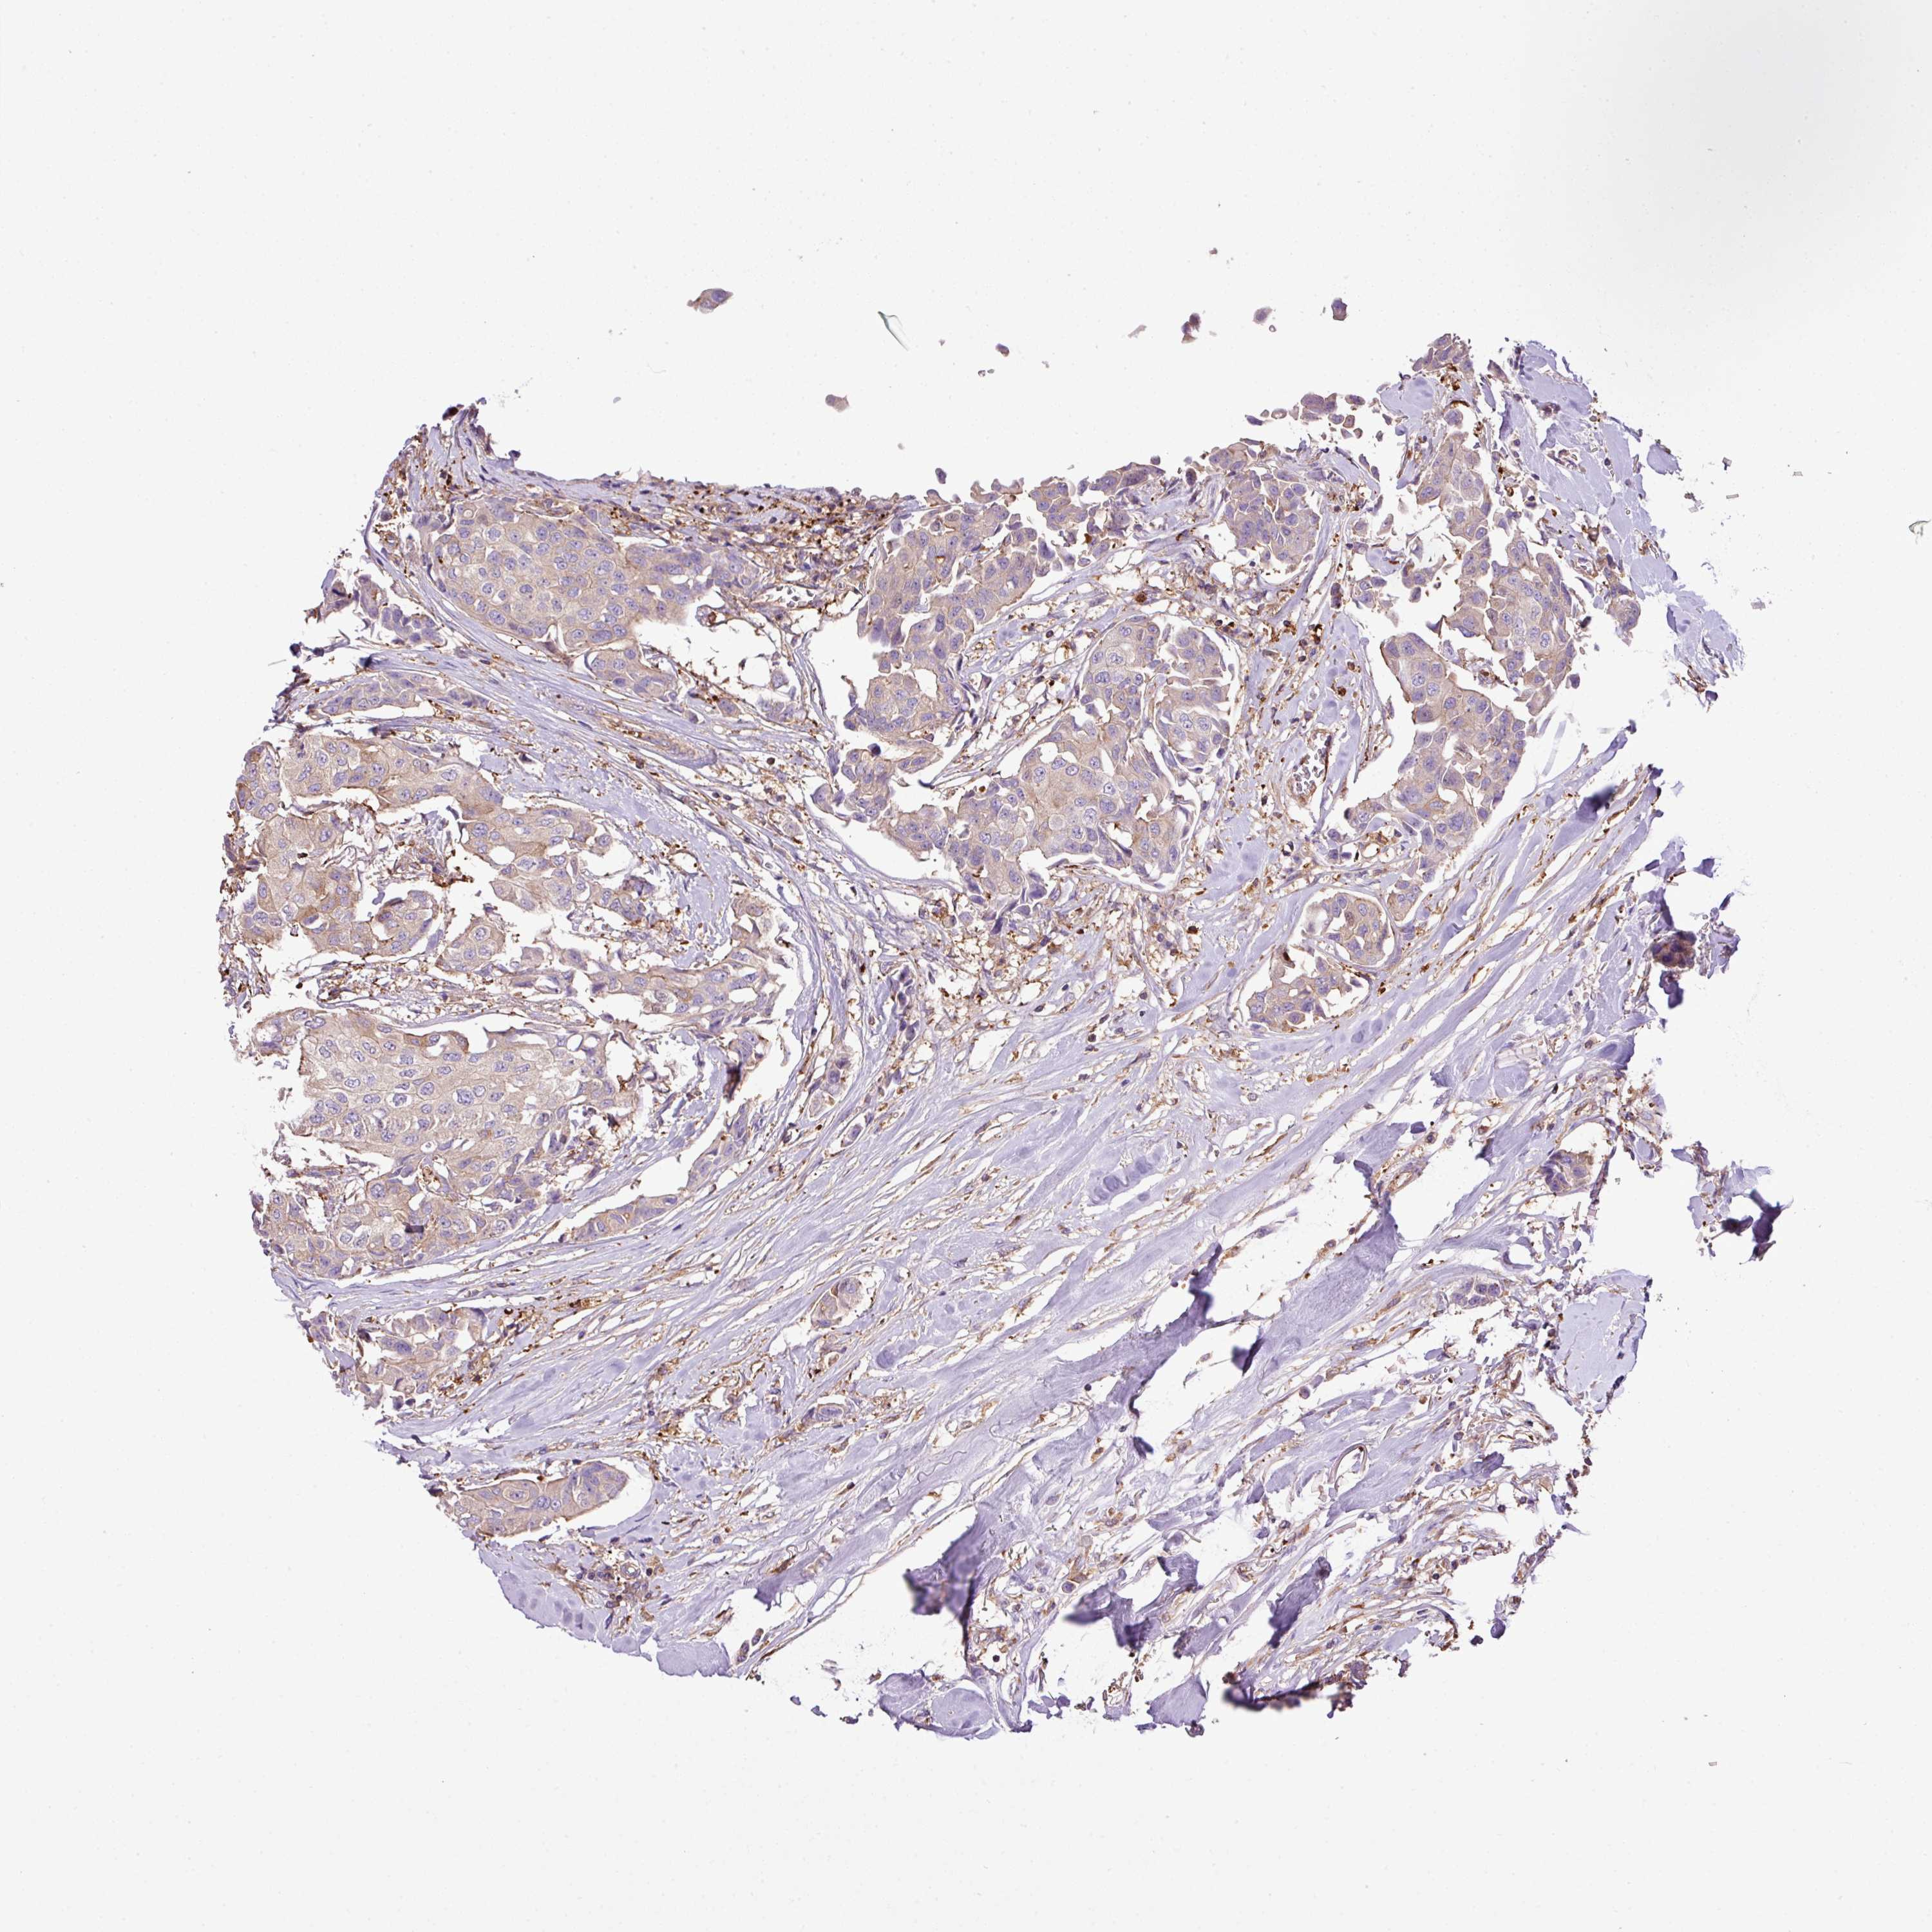

CANCER BREAST CANCER Show tissue menu

BRCA TCGA BRCA VALIDATION PROTEIN EXPRESSION